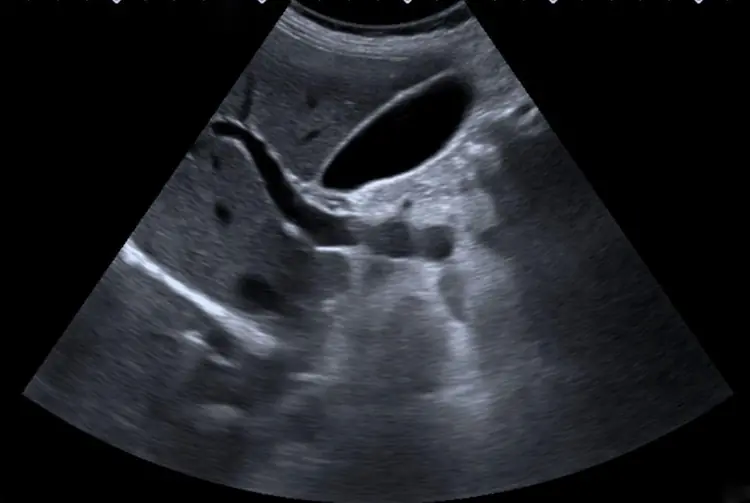

Occlusion : identifier le blocage en urgence.